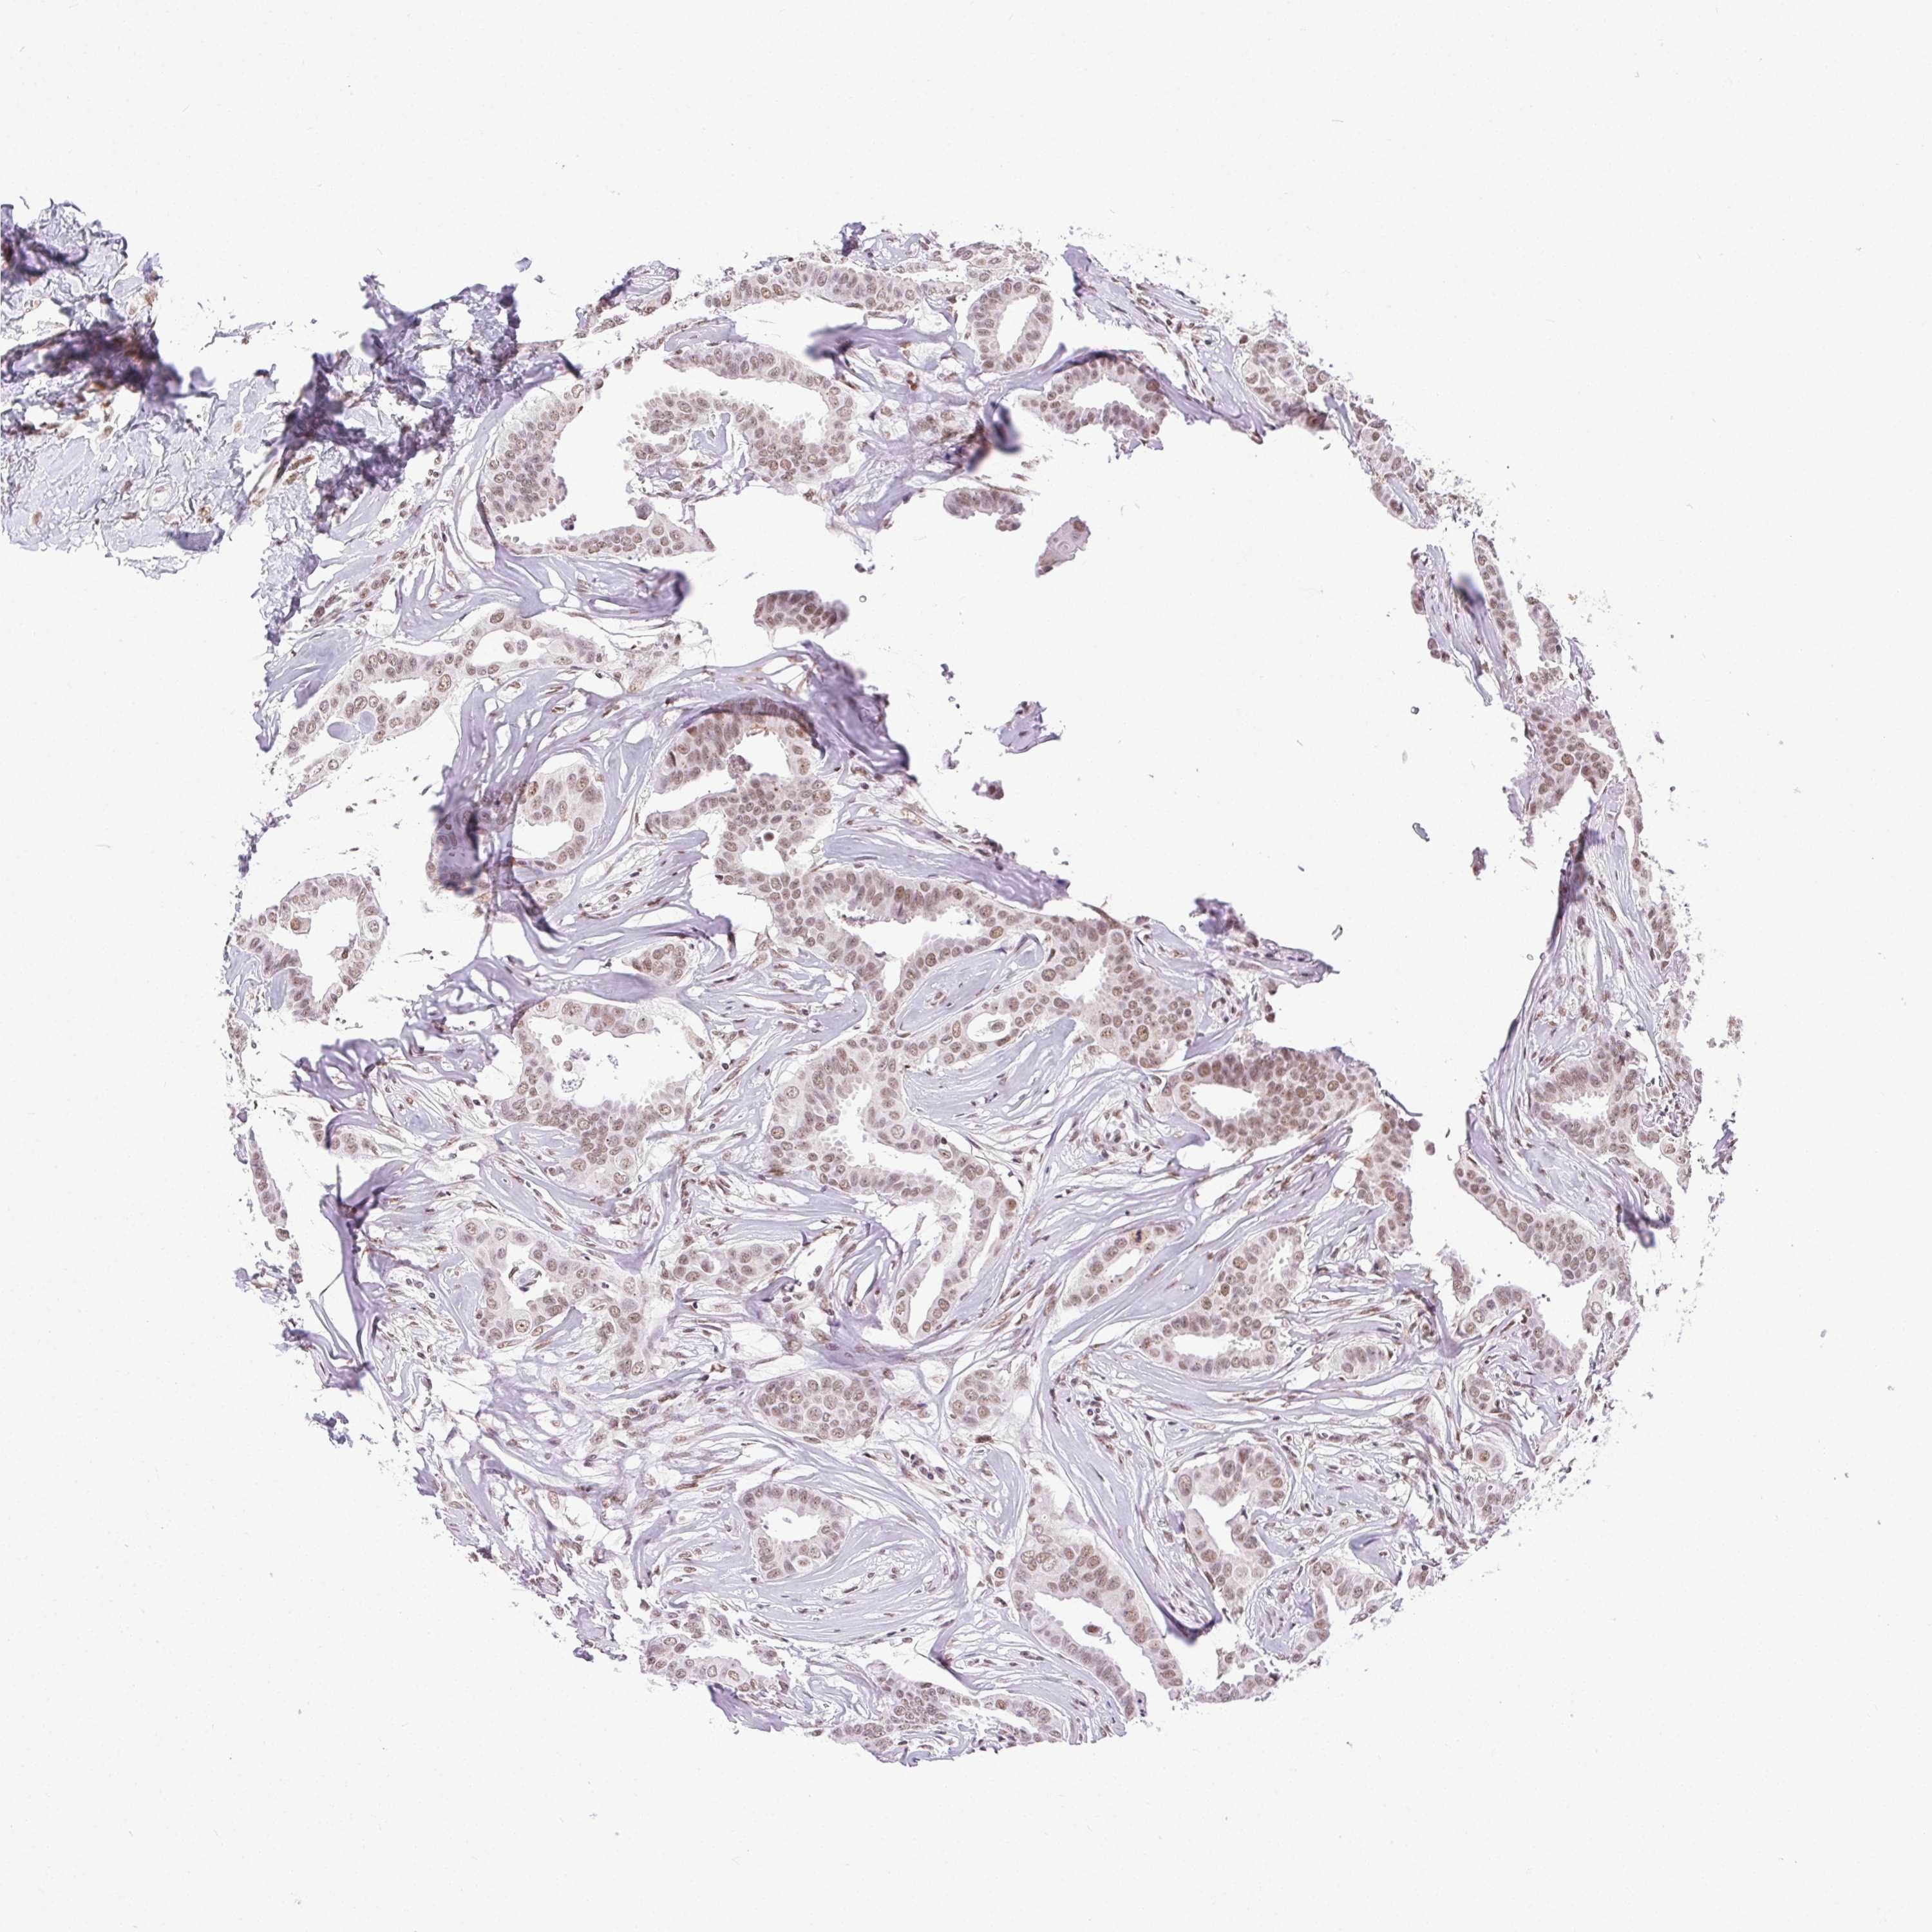

BRCA TCGA BRCA VALIDATION PROTEIN EXPRESSION